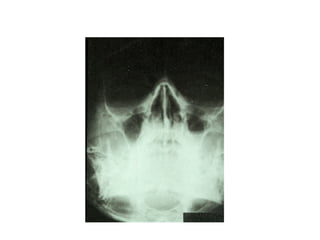

• X-rays – Water’s view (Occipito-mental view) – Air

fluid level or opacification

DIAGNOSIS • Transilluminationtest - Affected sinus  Opaque

• X-rays –Water’s view (Occipito-mental view) – Air fluid level or opacification